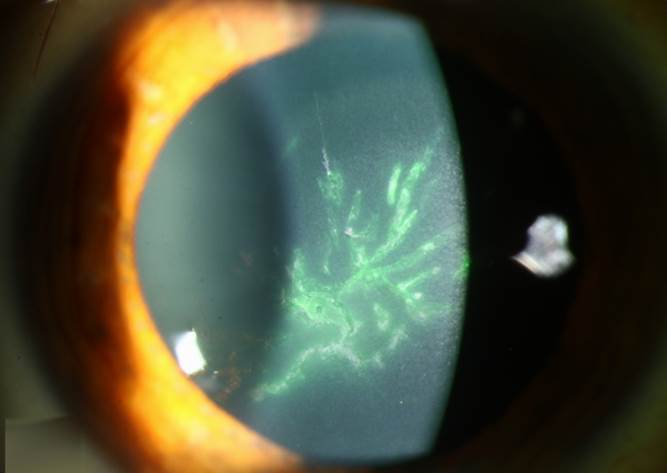

각막상피각막염은 실제 바이러스가 활성화되서 살아있는 상태로 소수포-> 가지모양 궤양(사진) -> 지도모양궤양(사진) -> 흉터 순으로 진행이되며 통증과 눈부심, 눈물, 시력감소와 같은 증상이 발생합니다. 또한 각막의 감각도 소실되거나 줄어들어 궤양정도에 비해서는 세균각막염보다 통증은 덜할수 있습니다. 치료는 감염상피를 제거하고 항바이러스제 안약을 점안해야하며 2-3주간 점안해야합니다. 스테로이드는 바이러스 활성을 증가시킬 수 있기 때문에 감염상피각막염에서는 사용하지 않는게 좋습니다.